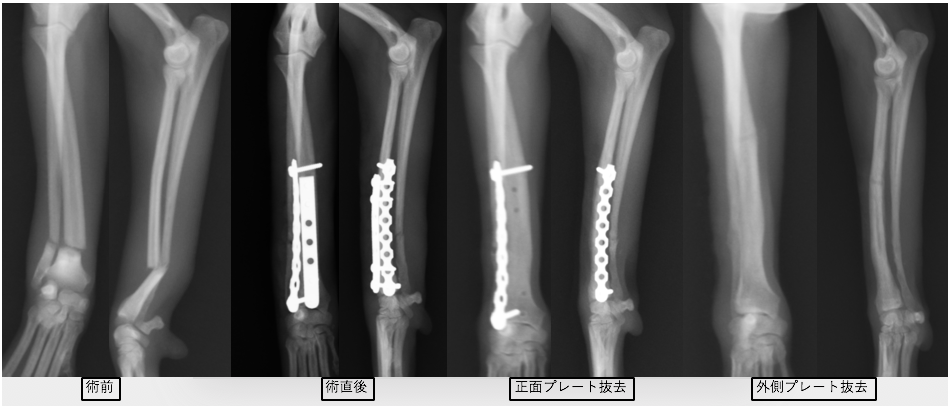

次の症例は11ヶ月のトイプードルで、スリングから飛び降りた後から足をケンケンするということで来院しました。左橈尺骨遠位斜骨折で、2日後に手術を実施しました。遠位骨折の場合尺骨(細い方の骨)には治療を行いませんが、骨折線も綺麗にあっているのがわかります。術後は次の日から足を着くことが可能で、1週間後に帰る時には通常に近い歩様で帰っていきました。その後1週間で抜糸となりますが、そこまでは散歩を5〜10分ほどにしてもらいます。ジャンプや激しい運動はしないでもらっています。その後2週間は散歩を15〜20分、その後1ヶ月は25〜30分で、その頃にプレートを1枚抜去します。

正面から見たレントゲン画像です。

横から見たレントゲン画像です。

術後のレントゲン画像です。足もまっすぐになり、尺骨という骨も綺麗にあっているのがわかります。